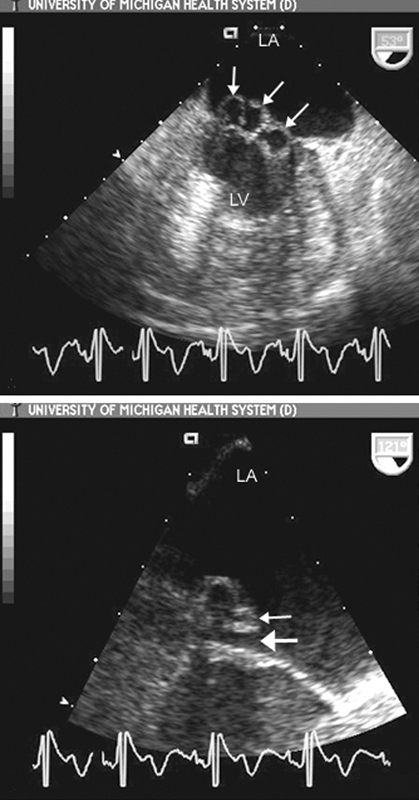

فحوصات تشخيصية لبعض امراض القلب والشرايين التاجية